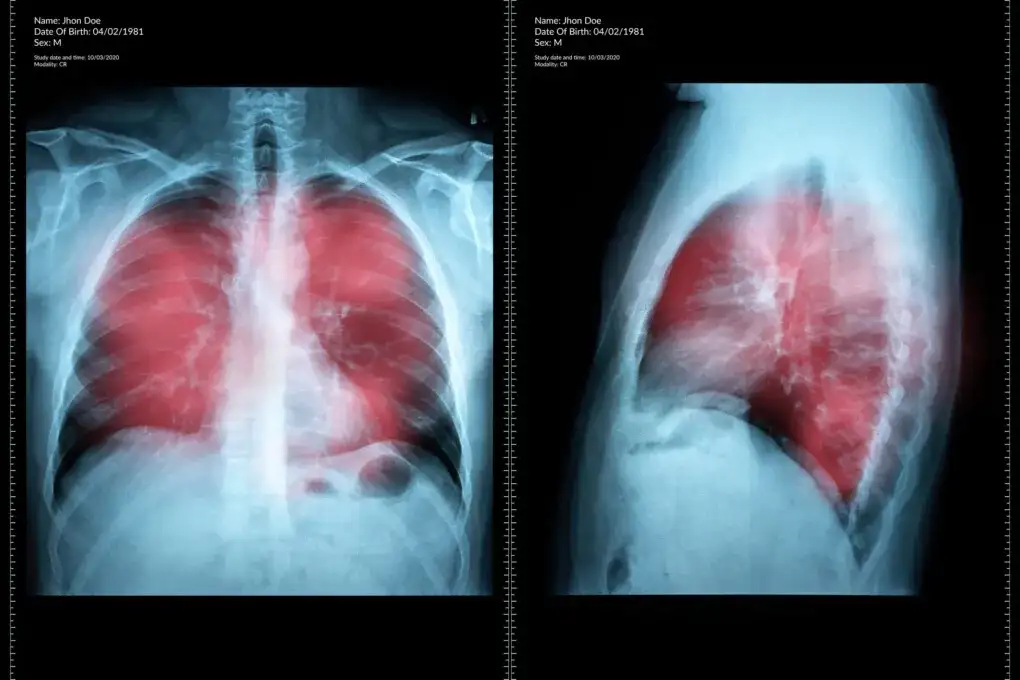

Diagnostyka raka płuc

Nowotwór płuc diagnostyka rozpoczyna się od dokładnego wywiadu lekarskiego i badania fizykalnego. Następnym krokiem jest wykonanie zdjęcia RTG klatki piersiowej, które może ujawnić niepokojące zmiany. Tomografia komputerowa pozwala dokładniej ocenić charakter i zasięg zmian.

W procesie diagnostycznym kluczową rolę odgrywa bronchoskopia i biopsja. Rak oskrzeli objawy można potwierdzić dzięki badaniu histopatologicznemu pobranej tkanki. Dodatkowe badania laboratoryjne pomagają określić stadium zaawansowania choroby.